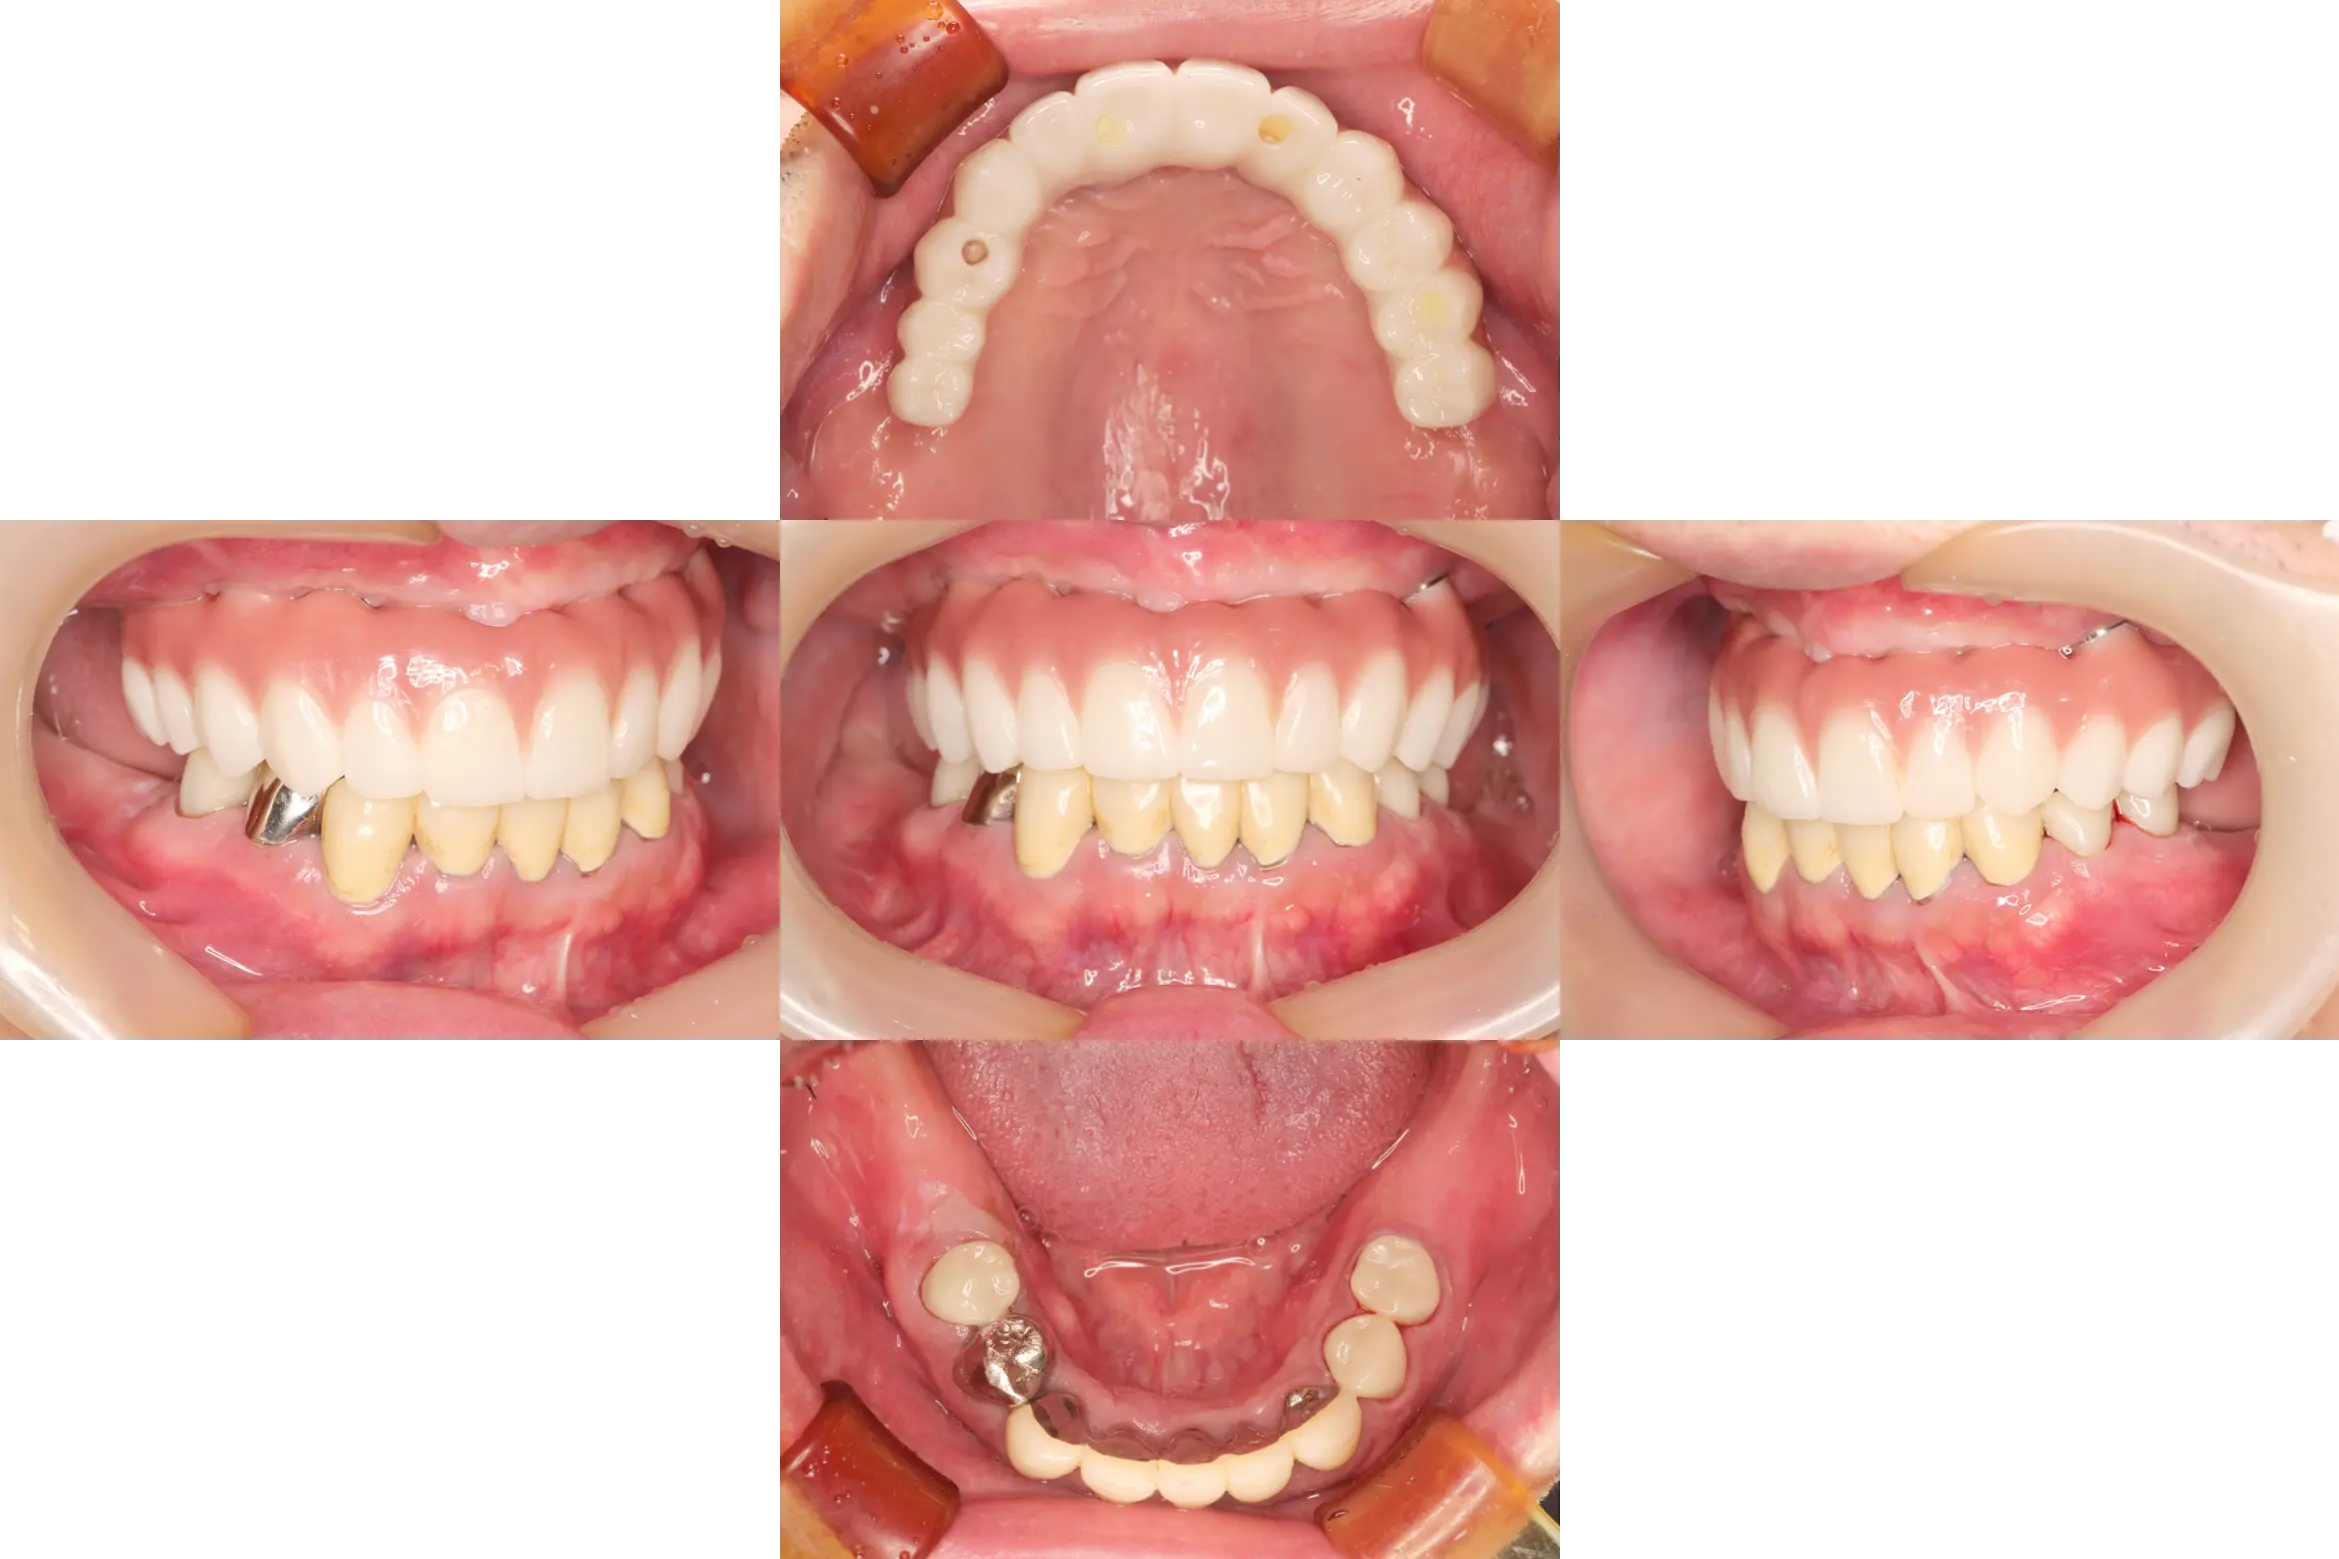

case11

症例11

| 治療ケース | インプラント埋入、オールセラミッククラウン、ファイバーポストコア、フレックスデンチャー、ボトックス注射。 |

| 症状 | 痛み、違和感。 |

| 治療結果 | 入れ歯の調子が悪く、他院で骨が少なくインプラント治療を断られたとの主訴でご来院。1次手術、2次手術を行いプロビジョナルを装着。上顎前歯はファイバーポストコアを築造、経過観察後、問題の無いことを確認して最終上部構造を装着。なんでもよく咬めるようになり、安定している状態です。 |

| 治療開始月 | 2023年12月 |

| 治療期間 | 約14ヶ月 |